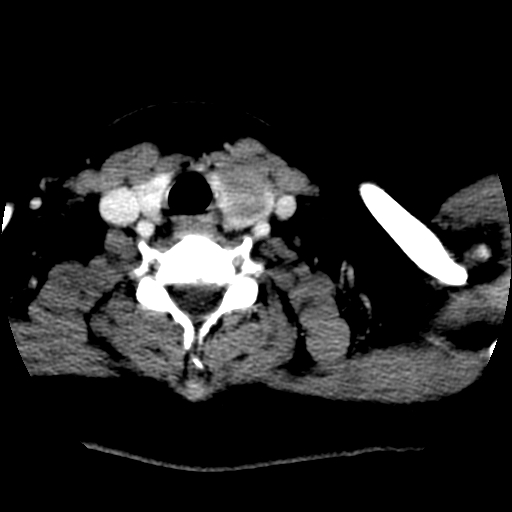

标题: CT25491:女,55岁,发现左侧甲状腺肿块一个月。 [打印本页]

标题: CT25491:女,55岁,发现左侧甲状腺肿块一个月。

女,55岁,发现左侧甲状腺肿块一个月,彩超示:甲状腺多发结节伴左叶结节液化。

边界清,无明显强化,考虑考虑甲状腺腺瘤